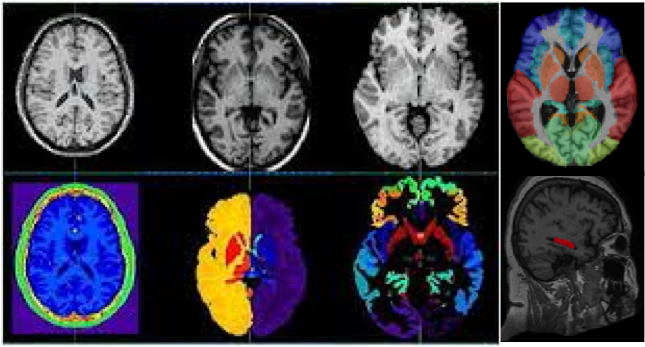

MARS (Multi-Atlas Robust Segmentation) Images

1 Images available.

Description:logo_v1